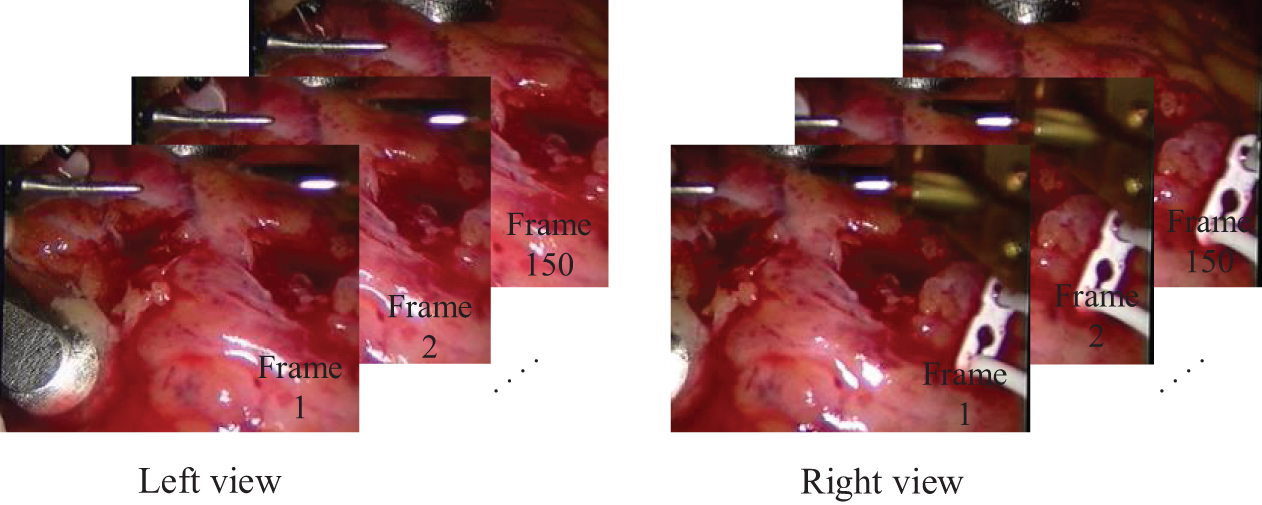

Fig. 5 illustrates sample frames from the processed real heart dataset, showing corresponding left and right views.

Figure 5: Sample frames from the real heart dataset